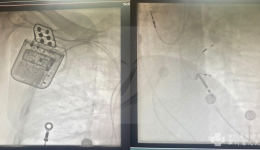

心血管内科成功开展省内首例准分子激光电极拔除术

3月6日,心血管内科田文杰、唐艺加团队,率先运用国际先进的308nm准分子激光技术,成功为一名复杂起搏电极感染患者实施省内首例激光电极拔除术,标志着我院心血管内科在心血管介入领域再次取得突破,彰显了心血管内科在复杂心血管疾病诊疗方面的领...